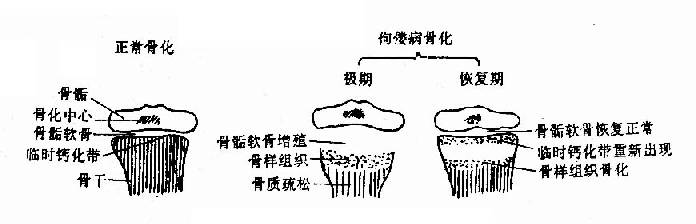

佝偻病的主要病理改是骨样组织增生,骨基质钙化不良。正常婴儿在其骨干与骨骺之

间有一条软骨带,称为“骺板”,在骨骼的末端,软骨细胞迅速生长(增殖带),而在骨干端成熟软骨细胞整齐排列成柱状,成骨细胞放出磷酸钙而形成新骨。佝偻病时,患者血磷或血钙降低,钙磷沉积于骨受阻,成骨作用发生障碍,长骨干骺端骺软骨中,成熟肥大的软骨细胞和成骨细胞不能正常钙化,形成骨样组织堆积于局部,致临时钙化带增厚,骨骺膨大;长骨骨干由于骨质脱钙,骨皮质为不坚硬的骨样组织代替,致骨干易弯曲畸形,甚至发生病理性骨折。颅骨则由于钙化障碍而发生软化,并由于骨样组织在骨膜下堆积而致方颅和颅骨畸形(图3-2)。

图3-2正常骨化和佝偻病时的变化

X线改变以骨骼发育较快的长骨为明显,尤以尺桡骨远端及胫腓骨近端更为明显,各期X线表现为(一)初期或轻症:改变不显著,干骺端钙化予备线可有轻度模糊,以尺桡骨端为明显,(二)激期或重症:干骺端钙化予备线消答,呈毛刷状,常有杯口状凹陷;骺线显著增宽,骨质稀疏,皮质变薄,可伴有不完全性骨折及下肢弯曲畸形。(三)恢复期:钙化予备线重新出现,但仍不太规则,杯口状改变渐消失,骨密度渐恢复正常。